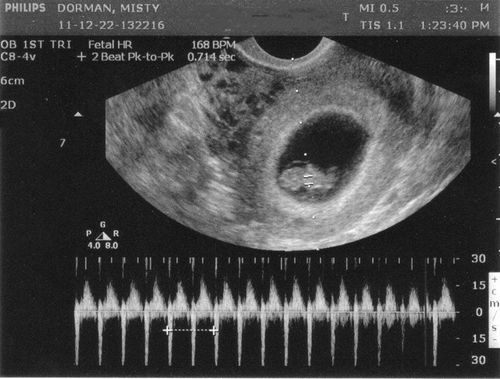

Siêu âm tim thai là một phương pháp chẩn đoán bằng hình ảnh trong giai đoạn tiền sản, sử dụng sóng siêu âm kiểm tra cấu trúc, chức năng và tần số tim nhằm đánh giá tình trạng tim mạch của thai nhi.

Trong quá trình phát triển của thai nhi thì tim bắt đầu hình thành khá rõ và đập vào ngày thứ 22 sau khi thụ thai, thường trước cả khi mẹ nhận ra mình có thai. Tim thai sẽ xuất hiện vào tuần thứ 6-7 của thai kỳ, trong giai đoạn này nếu sử dụng các phương tiện hiện đại thì đã có thể nghe thấy nhịp đập của tim thai nhưng cũng có một số trường hợp phải tới tuần thứ 8-10 của thai kỳ thì mới nghe được tim thai phụ thuộc vào sự phát triển của phôi thai.

Tim của thai nhi sẽ phát triển từ hình dạng ống đơn giản rồi xoắn và phân chia để hình thành nên trái tim có 4 buồng và van tim là cấu trúc hoàn thiện nhất. Bắt đầu từ tuần thứ 20 thì nhịp đập của thai trở nên mạnh mẽ và chỉ cần dùng tai nghe bình thường đã có thể nghe được tim thai. Đây chính là thời điểm có thể đánh giá tim thai nhờ vào siêu âm 4D để xác định vị trí, kích thước, hình thái nhằm đưa ra chẩn đoán về tình trạng tim thai.

4. Nhịp tim thai như thế nào là bình thường?

Nhịp tim thai thông thường sẽ dao động trong khoảng từ 120-160 lần/phút nhưng khi chuyển động trong bụng mẹ có thể tăng lên tới 180 lần/phút. Tim thai sẽ đập nhanh hơn vào tuần thứ 20 nhưng nếu quá 180 lần/phút thì có thể là dấu hiệu bất thường cần được kiểm tra.